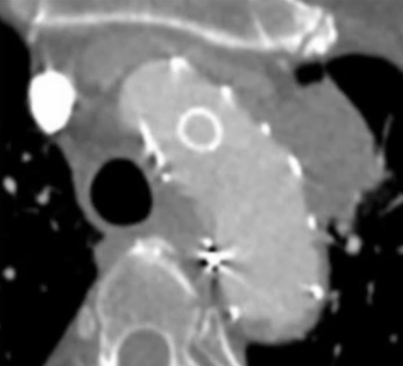

★ 左锁骨下动脉重建

从左侧肱动脉导入可调弯鞘送至左锁骨下动脉近端,同样使用asahi treasure 12导丝和支撑导管顺利通过覆膜区。依次送入4mm、6mm和8mm球囊对局部进行扩张。

将支架送入覆膜区约1cm释放支架。之后,更换更大口径的球囊送至主动脉弓内进行后扩张,使支架呈喇叭口状,以稳定两者结构,减少内漏的发生。由于左锁骨下动脉位于假性动脉瘤的破口位置,此处使用球扩覆膜支架实现了更加精准的定位,有效降低了内漏风险。

球囊回收时

带鞘进开窗口

置入VBX11-29mm支架,支架伸入

覆膜支架约1cm后释放并球扩塑形

★ 术后造影

支架释放完毕后,分别进行左前斜和右前斜造影。结果显示,支架形态良好,左侧颈总动脉和左锁骨下动脉分支血流通畅。右前斜位可见假性动脉瘤封闭完全,仅有少量内漏,考虑与膜渗相关。同时行颅内动脉造影,结果显示双侧颈动脉、双侧椎动脉以及颅内血管显影良好。结果表明,手术成功实现血管重建,假性动脉瘤有效封堵,且未对脑部供血造成不良影响。